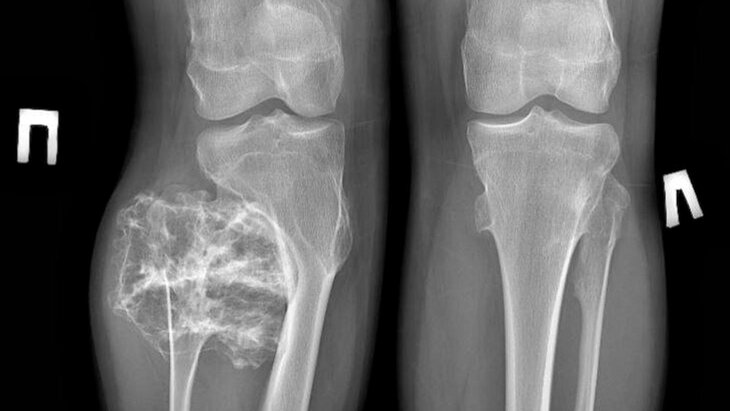

Врачи Московской областной детской клинической травматолого-ортопедической больницы удалили 15-летнему подростку опухоль в ноге размером 9 сантиметров, сообщает телеканал "360" со ссылкой на пресс-службу министерства здравоохранения Подмосковья.

У подростка выявили твердое новообразование в области малоберцовой кости. Обследование показало, что это остеохондрома – образование, покрытое хрящевой "шапочкой", которое часто возникает в детском и подростковом возрасте.

Как пояснил травматолог Сергей Хохлов, подобные опухоли нередко выявляют случайно из-за отсутствия боли и дискомфорта.

"К сожалению, у данного заболевания не бывает обратного развития и единственный метод лечения – хирургический. В ходе операции мы успешно удалили опухолевидное образование в пределах здоровой костной ткани", – поделился врач.